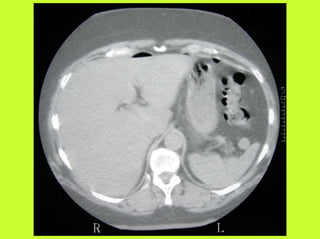

3) RADIO (PNO)

RADIOGRAPHIES

ABDOMEN SP -scanner

PNEUMOPERITOINE SUR SUJET DEBOUT

" Croissant gazeux sous diaphragmatique

" Disparition du niveau hydroaérique gastrique

PNEUMOPERITOINE SUR SUJET COUCHE

" Visibilité du ligament triangulaire du foie

" Visibilité anormale des parois intestinales

" Image aérique pré-hépatique

"Pneumatisation de MORRISSON

(cul de sac inter-hépato-rénal)

AUTRES EXAMENS

"TOGD aux hydrosolubles?

" Echo, scanner

" Coelioscopie ?

" Pas de lavement colique, pas de fibroscppie, pas de coloscopie, pas

d’IRM